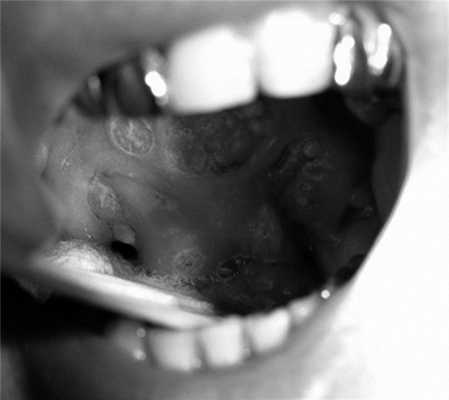

С 05.03.13 по 16.05.13 проведено одновременное химиолучевое лечение в разовой очаговой дозе (РОД) 2 Гр до СОД 70 Гр с цетуксимабом (стартовая доза 800 мг, далее 1 раз в неделю, поддерживающая доза 500 мг) (см. рис. 2). В процессе терапии имели место выраженные лучевые реакции в виде мукозита III степени RTOG, проявившиеся на ранних сроках (СОД 24 Гр), которые потребовали незапланированного перерыва в лечении в течение 14 календарных дней (СОД 40 Гр) (рис. 3). Рис. 3. Клиническая картина динамики мукозита в процессе лечения. Также отмечались характерные для таргетного препарата кожные реакции в виде папулезно-пустулезных высыпаний на коже лица, головы, груди, шеи, максимально выраженные до III степени через 2 дня после 4-го введения цетуксимаба, на фоне дерматита лица и шеи II степени в проекции полей облучения (рис. 4). Рис. 4. Клиническая картина динамики дерматита в процессе лечения. Пациенту проведены облучение в полном объеме, а также все запланированные введения цетуксимаба.

При осмотре через 1 нед после окончания химиолучевой терапии клинически экзофит опухоли не определялся. Отмечено стихание мукозита до I степени RTOG и дерматита до I степени RTOG (см. рис. 3, 4). Далее еще через 1 нед лучевые реакции стихли полностью. По данным контрольного обследования через 1,5 мес получены данные, подтверждающие полный эффект, признаков остаточной опухоли не выявлено. Пациент оставлен под наблюдением. В поздние сроки единственным негативным последствием являлась ксеростомия I степени RTOG, не мешающая пациенту жить и работать в привычном ему до болезни ритме. В настоящее время безрецидивный срок наблюдения пациента составляет 6 лет.